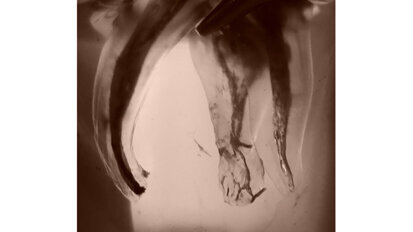

Hybridní terapie alignery